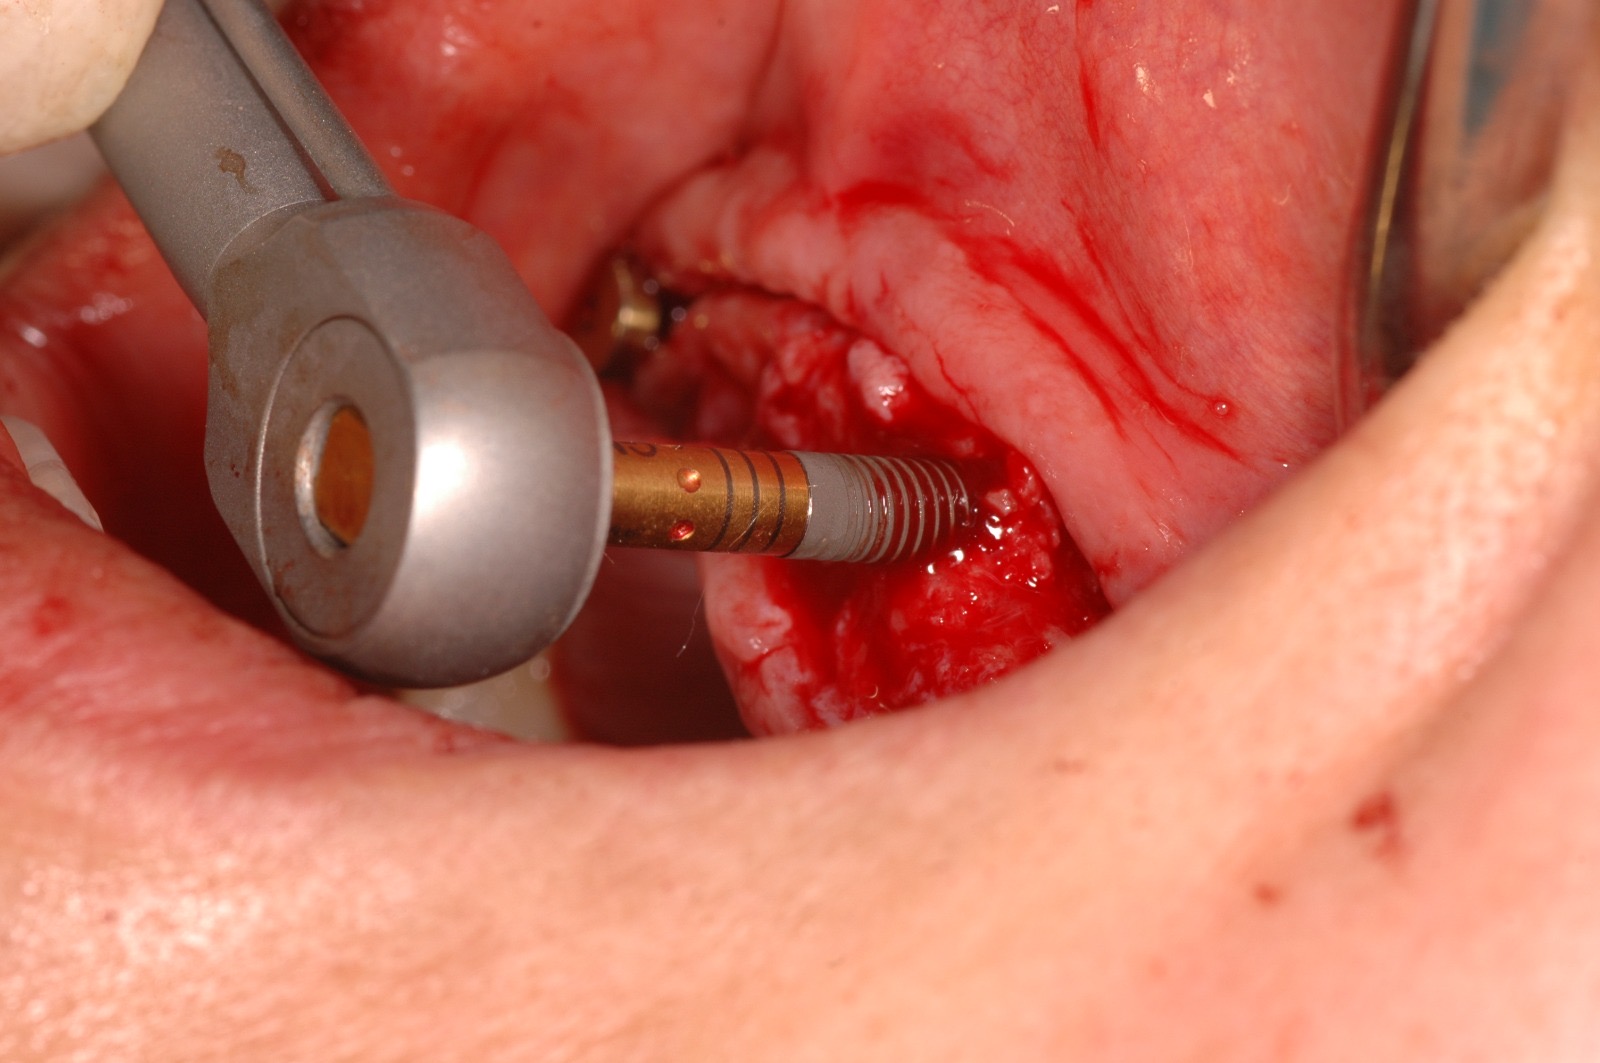

¿Sabías que la colocación de implantes dentales ya no es como antes? Gracias a los avances tecnológicos, este procedimiento es ahora más preciso, cómodo y seguro.

Olvídate de las intervenciones invasivas y las largas recuperaciones. En este caso clínico, te mostraremos cómo la tecnología digital se une a la experiencia de nuestros especialistas para lograr resultados sorprendentes.